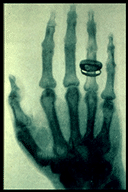

In his discovery Roentgen found that the X-ray would pass through the tissue of humans leaving the bones and metals visible. One of Roentgen’s first experiments late in 1895 was a film of his wife Bertha's hand with a ring on her finger (shown below on right). The news of Roentgen’s discovery spread quickly throughout the world. Scientists everywhere could duplicate his experiment because the cathode tube was very well known during this period. In early 1896, X-rays were being utilized clinically in the United States for such things as bone fractures and gun shot wounds.

Take a look at these early x-rays.